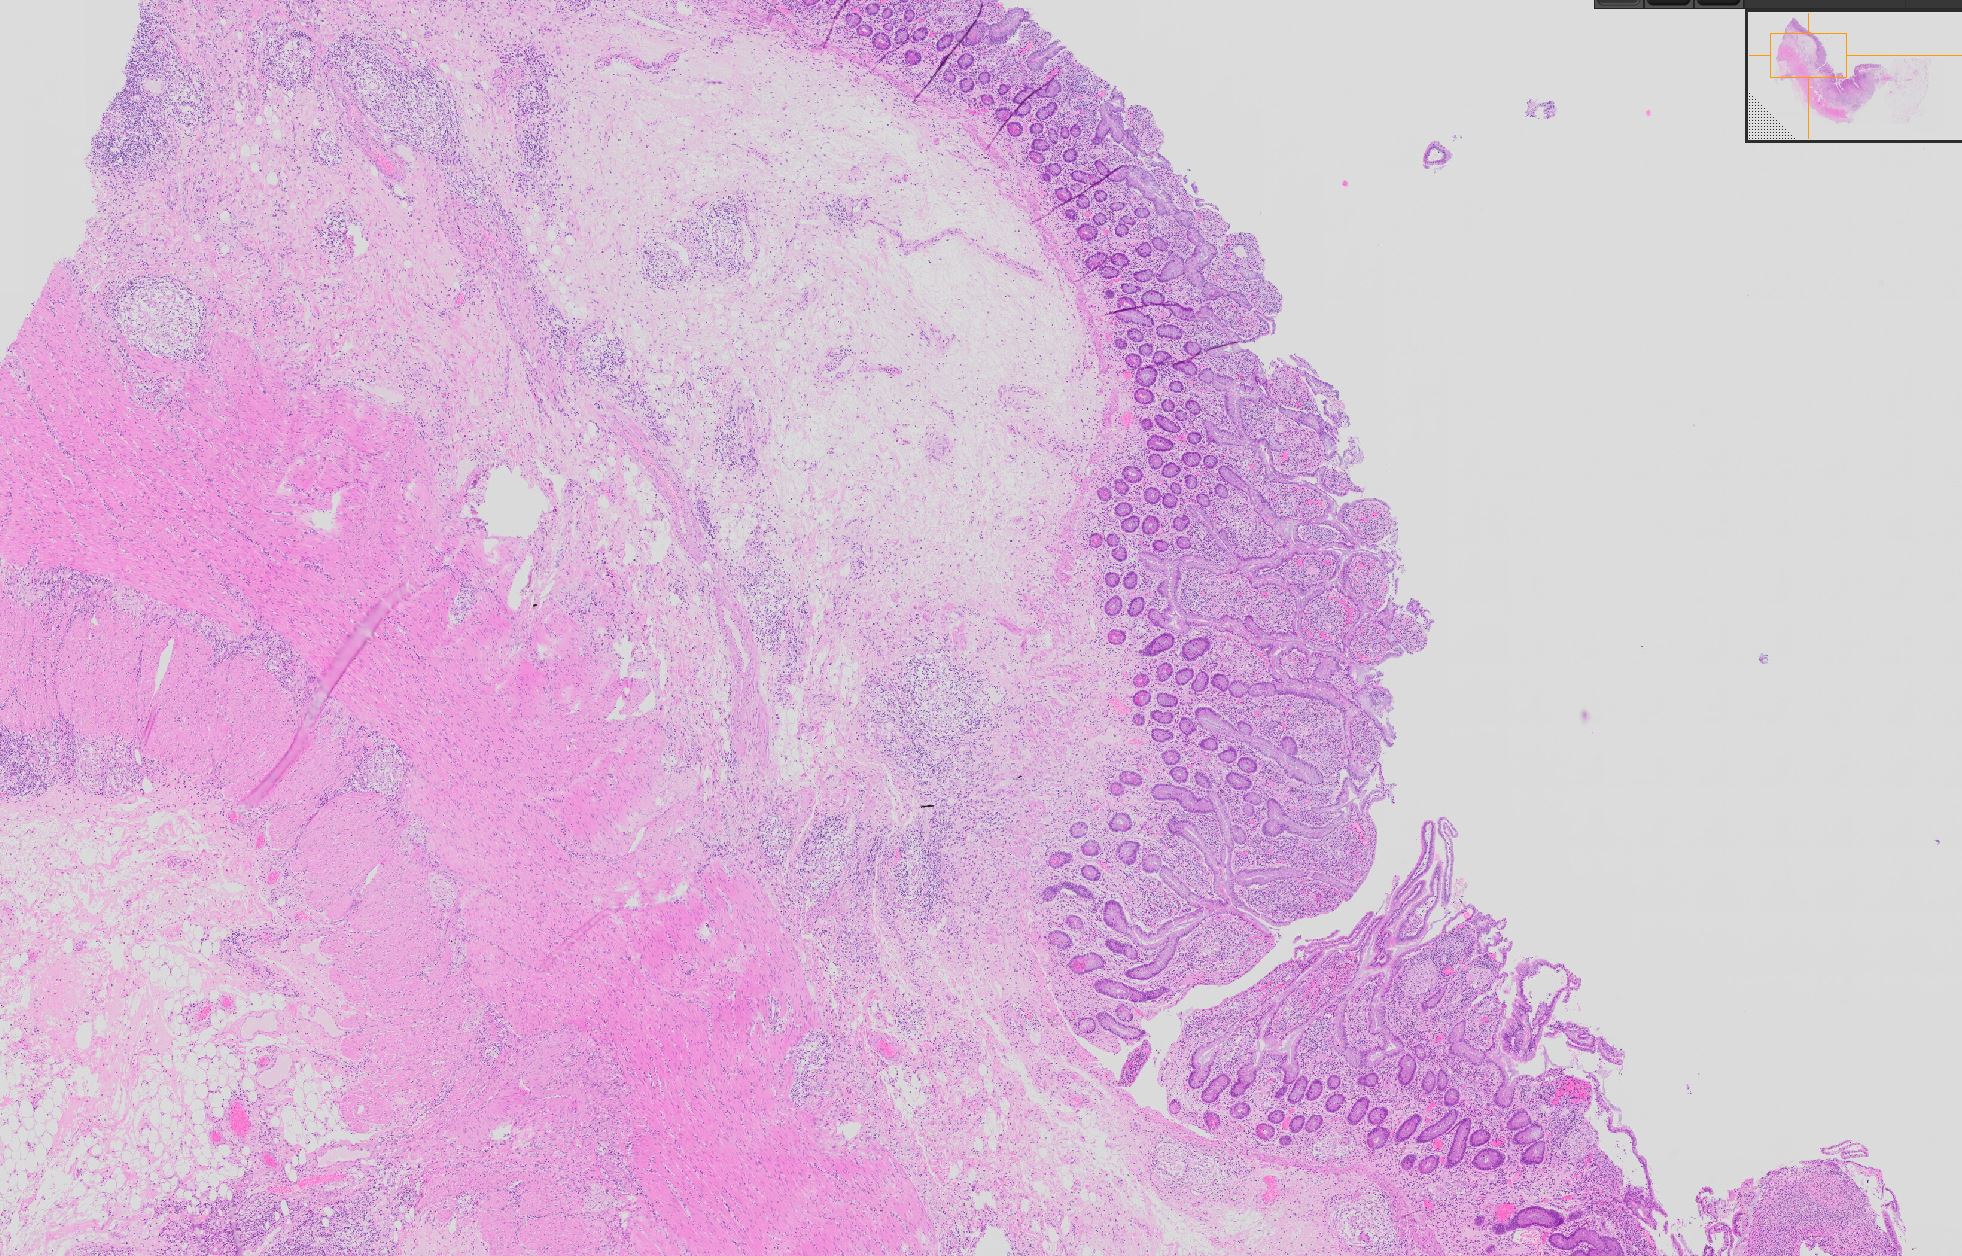

Morbus Crohn

Ileum terminal

Abflachung der Dünndarmzotten oder Verplumpung der Dünndarmzotten (=Architekturstörung als Zeichen der Chronizität).

Zahlreiche  epitheloid-riesenzellige Granulome in allen Wandschichten.

Morbus Crohn des Dünndarms. Status nach Hemikolektomie rechts. Parailealer Abszess. Ileokoloische Resektion.